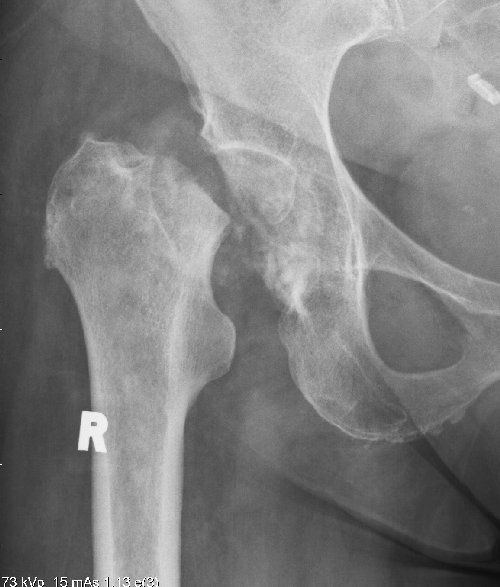

Avascular Necrosis

This is a condition caused by a failure of the blood supply to a part, or the whole, of the femoral head. As the bone is exposed to daily trauma it cannot regenerate and may start to collapse. The extent of the collapse is variable, healing will solidify the head but may lead to a mis-shapen head and therefore early osteoarthritis.

In extreme cases the whole femoral head may fragment and the bone dissolves away.

31/03/2011